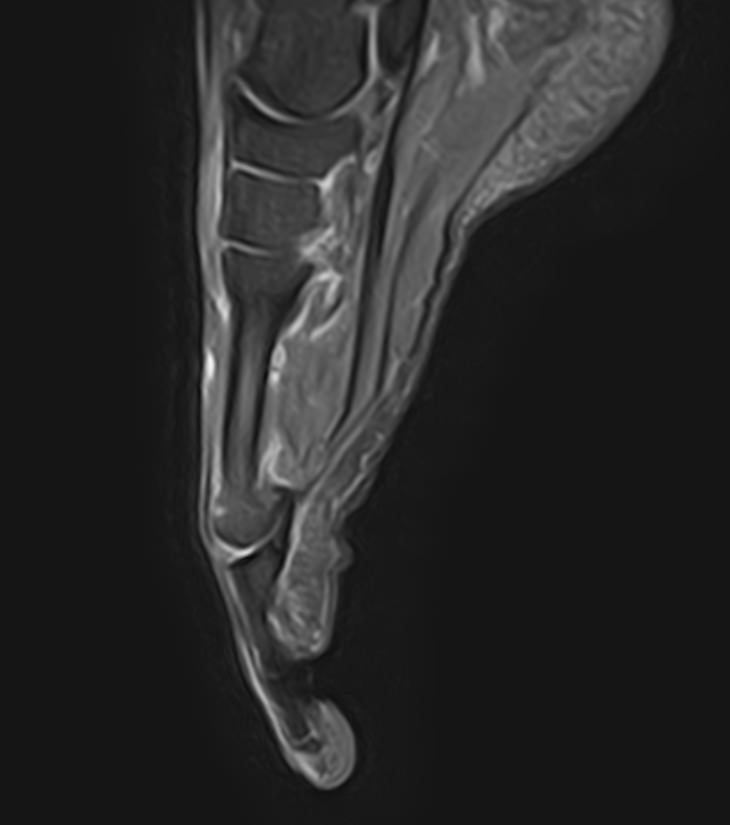

В клинике «Доступная медицина» данное исследование проводится на современном высокопольном магнитно-резонансном томографе экспертного класса TOSHIBA VANTAGE TITAN 1,5 Тесла. Напряженность магнитного поля 1,5 Тесла обеспечивает высокую разрешающую способность аппарата, что позволяет выявлять минимальные изменения в тканях и диагностировать заболевания на начальной стадии.

В большинстве случаев проводится стандартная магнитно-резонансная томография стопы без использования контраста, однако в некоторых случаях требуется контрастное усиление для детализации патологических очагов. Для этого применяется контрастное вещество на основе гадолиния (элемент, относящийся к редкоземельным металлам), которое полностью выводится из организма в течение суток преимущественно почками.